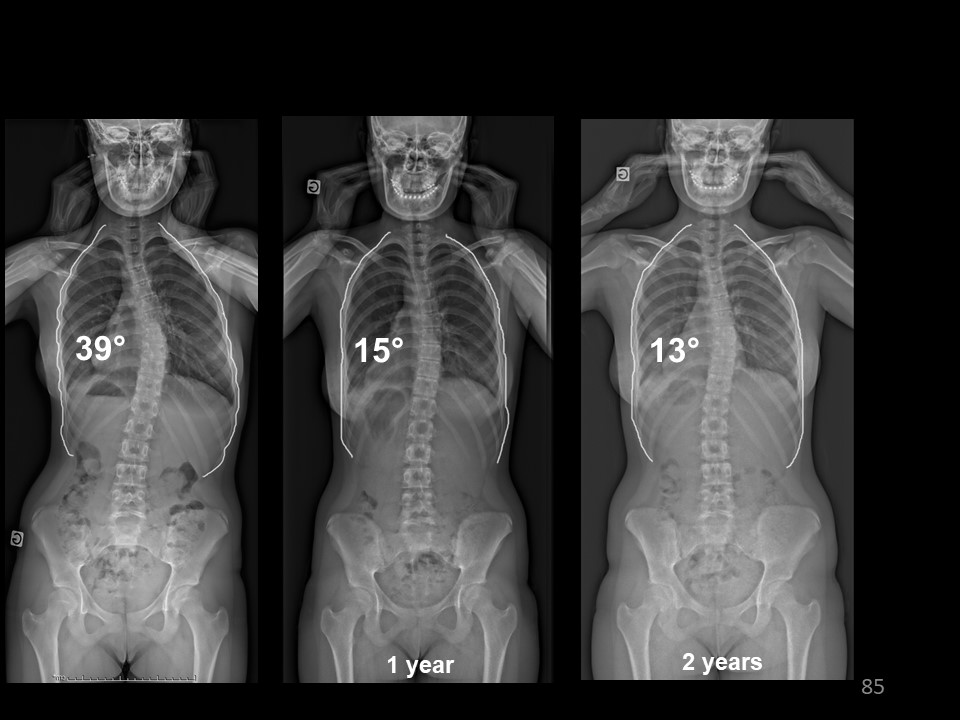

Here is the result of this case n° 90, with initially thoracic scoliosis of 39° and rib hump of 17° ATR. Excellent in-brace correction with total reduction of the curvature. The sagittal plane is also improved, |

|

Under EOS 3D, detorsion is excellent with centring of the vertebrae on the midline |

Here is the Clinical picture in brace. |

At Risser 5, after 2 years of bracing, the angulation is 13°, |

Clinical aspect at the end of treatment after 6 months of nighttime bracing The Bunnel ATR is under 10°. |